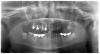

lag-nsi Опубликовано 22 января, 2013 Автор Поделиться Опубликовано 22 января, 2013 Повторю и вопрос:Уважаемые специалисты!Помогите советом по плану протезирования.Справа на 4 и 5-ке стояла коронка слитная и отдельная на 6-ке. При снятии коронки в ноябре 4-ку сломили.Появились боли на нёбе внурти, после чего удалили 5-ку, перфорация корня вкладкой (8 лет стоят в таком состоянии). Сейчас идёт речь об удалении 6-ки. В одном корне отломок инструмента, на другом разрежение костной ткани и говорят что он мягкий.Два варианта предлагают: имплантация 5, 6 без операции синус-лифтинг, имплантация с операцией.Ранее, в 2004 году на этой стороне была операция радикальной гайморотомии, одонтогенный гайморит правой верхнечелюстной пазухи, тотальное затемнение, отломки после удаления 7-зуба, пломбировачный 6-го.Пожалуйста посоветуйте, что лучше в моей ситуации? Не знаю что делать, боюсь операции. Заманчиво, что без операции предлагают имплантацию.И съёмник не хочу.Уже хожу три месяца без коронок.Вопрос у меня стоит о правой стороне.Делать одновременно и слева дорого для меня. Ссылка на комментарий